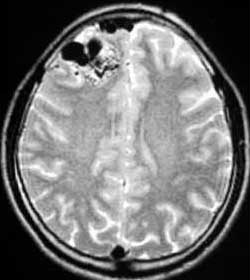

三、闭塞性脑血管病

----闭塞性脑血管病,如急性脑梗塞引起的偏瘫、颈动脉或椎基底动脉狭窄所致短暂性脑缺血发作(TIA)及可逆性神经 功能障碍(RIND),视网膜中央动脉或中央静脉闭塞引起的视力减退,静脉窦血栓性形成引起的颅内压增高等,均可通过 血管内的介入治疗得以改善,介入治疗的方法分溶栓、血管成形术或支架置入,根据病变选择不同的治疗方法。

5.急性静脉卒颅内静脉窦血栓形成静脉窦内溶栓治疗: 急性脑静脉卒中和颅内静脉窦血栓形成,由于缺乏典型的临床表现与体征,往往被误诊。当MRI显示轻至重度脑水肿,头痛 迟钝、颅压在5.33kPa(40mmHg)以内时均是溶栓的适应证。若已有大面积水肿和(或)出血,患者已昏迷,即使窦内溶栓 成功,但仍不可避免死亡。